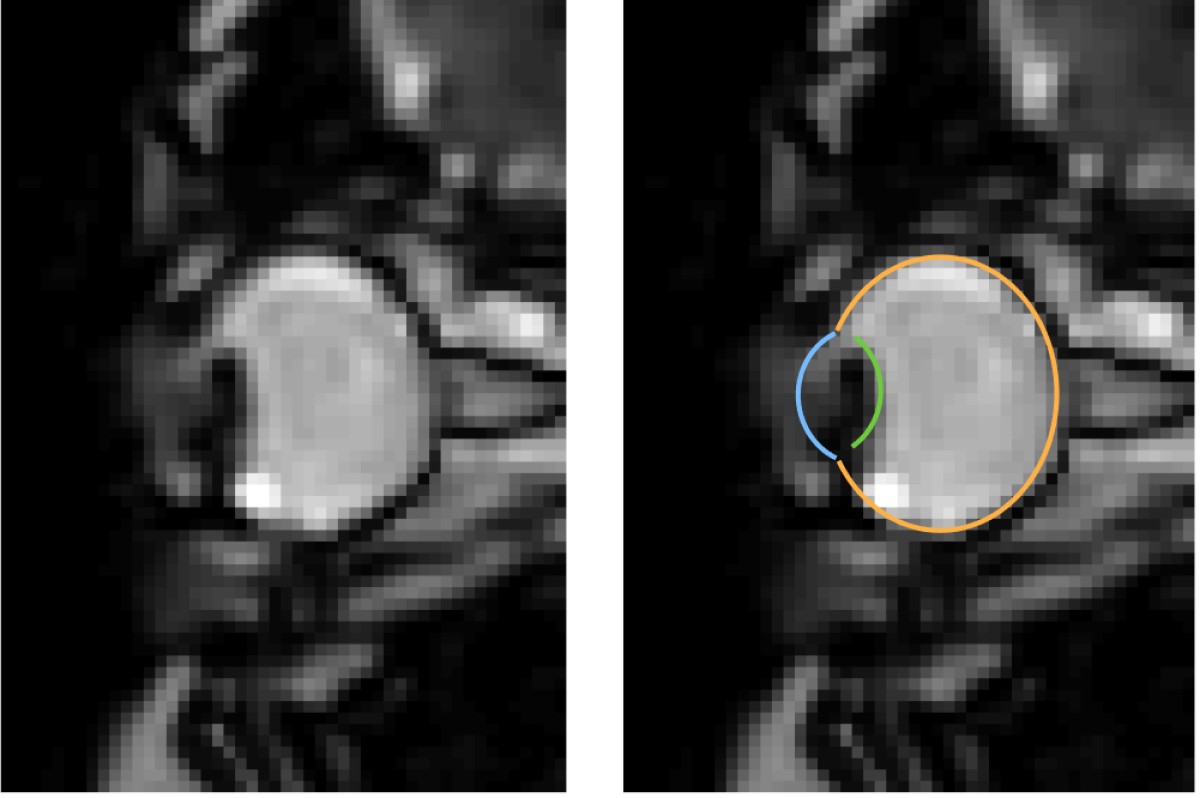

MRI images of eye movements during blinking: The eye is pulled back into the eye socket. The left image shows only the dynamic MRI data, the right image additionally shows the segmentation of the eye by the MREyeTrack. The photo corner consisting of six images shows the eye movement.© WWU - Johannes Kirchner

MRI is a relatively slow procedure, the temporal resolution usually ranges between seconds or minutes. Eye movements on the other hand are fast and typically last only a few dozen milliseconds. Recent technological advances allowed the recording of 2-D MR images at a resolution of up to 20 milliseconds. Those ultrafast MR sequences were initially developed for cardiac imaging and haven’t been applied to the recording of eye movements. “We could reach a temporal resolution of 35 milliseconds. Total scan duration of only a few minutes already leads to the acquisition of over 10000 images. For actual eye-tracking, a fully automatic segmentation algorithm to analyse these images was needed”, explains co-author Prof. Markus Lappe, professor for cognitive neuroscience at the Institute of Psychology at the University of Münster. “With ‘MREyeTrack’ we have developed such a segmentation algorithm, which allows the fully-automated analysis of eye position and orientation in every single image.”